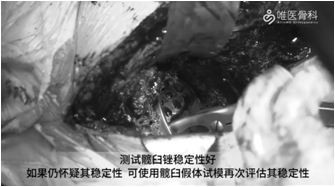

髋臼制备:磨锉髋臼,磨锉过程中要注意保留骨量,过多的磨削会累及髋臼边缘造成节段型缺损。本病例起初用65mm髋臼锉测试稳定性不佳,然后使用67mm髋臼锉,边磨锉边观察其与宿主骨的关系,然后进行反锉压实。测试髋臼锉稳定性好,如果仍怀疑其稳定性,可使用髋臼假体试模再次评估其稳定性。